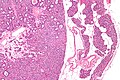

Chief cell parathyroid adenoma (left of image) and unremarkable parathyroid gland (right of image). H&E stain. (WC) | |

| LM | proliferation of parathyroid cells (chief cells, oxyphils or both) usually lacking adipose tissue, +/-rimmed by normal parathyroid gland, lack of destructive invasion of surround structures, lack of metastatic disease |

- Proliferation of parathyroid cells (chief cells, oxyphils or both) usually intermixed lacking adipose tissue.

- +/-Rim of normal parathyroid gland around the lesion[7] with adipose tissue.

Oxyphil parathyroid adenoma

Features:[2]

- Oxyphil cells:

- Large cells.

- Abundant cytoplasm.

DDx:

- Hürthle cell adenoma of the thyroid gland.